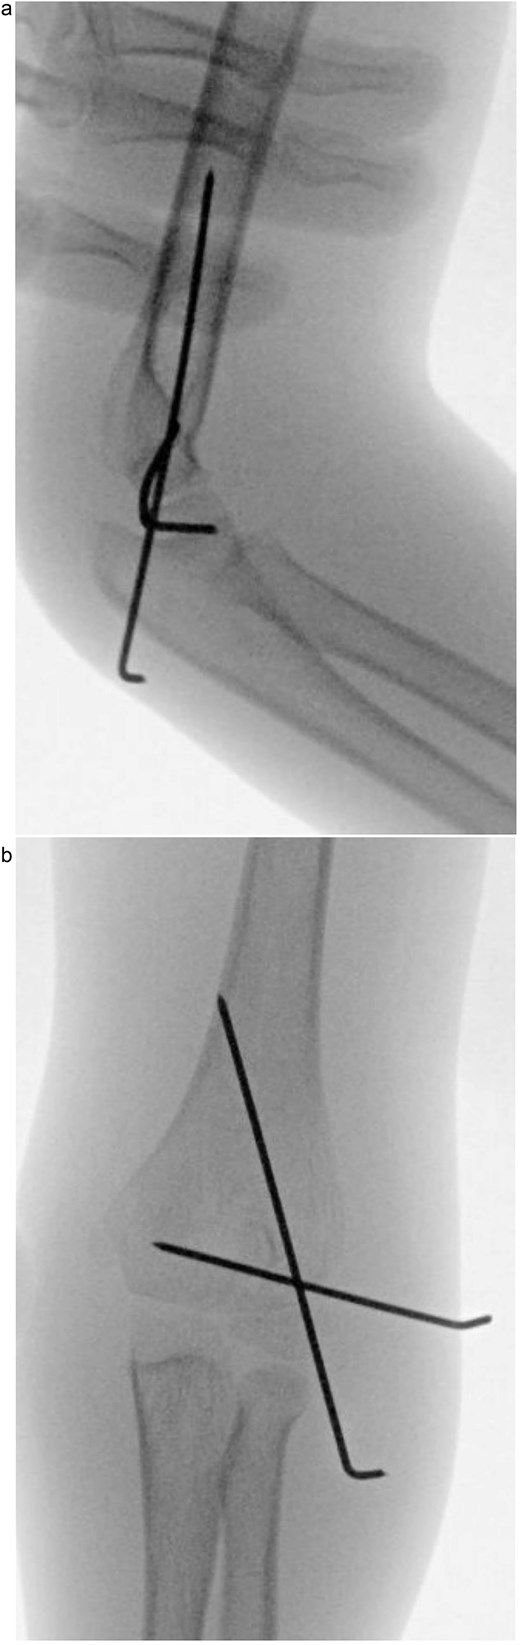

An 8-year-old boy presented to the emergency department with severe left elbow pain and deformity after falling while playing football. He reported landing on his arm but could not recall the exact elbow position. Examination showed significant swelling, deformity, and lateral elbow tenderness. The skin was intact, distal pulses and capillary refill were normal, and neurological assessment confirmed intact radial, ulnar, median, and anterior interosseous nerve function. Radiographs in anteroposterior and lateral views, along with a 3D CT scan, demonstrated a posteromedial dislocation of the elbow associated with a displaced fracture of the lateral condyle of the humerus (Fig. 1a).

(a) Pre-reduction anteroposterior radiograph of the left elbow showing posteromedial dislocation of the ulnohumeral joint with displaced lateral humeral condyle fracture. (b) Lateral radiograph demonstrating posterior displacement of the olecranon and lateral condyle fragment.